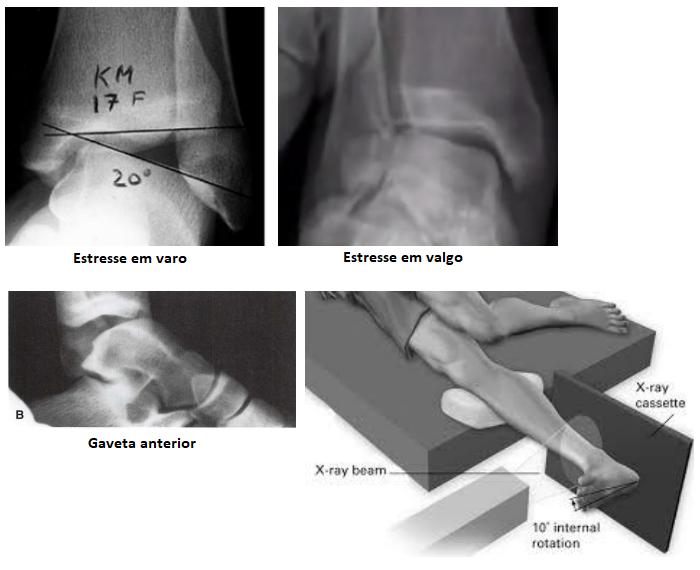

• RX sob estresse em varo, valgo e gaveta anterior

• Varo → avalia o complexo ligamentar lateral

• Valgo → avalia o complexo ligamentar medial + sindesmose

• Gaveta anterior → avalia o complexo anterolateral

• O estresse gravitacional pode ser realizado em varo e valgo também